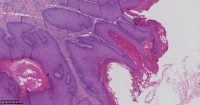

脂溢性角化症?

性别

女

年龄

61岁

一般病史

背部皮肤包块

标本名称

图1

脂溢性角化病